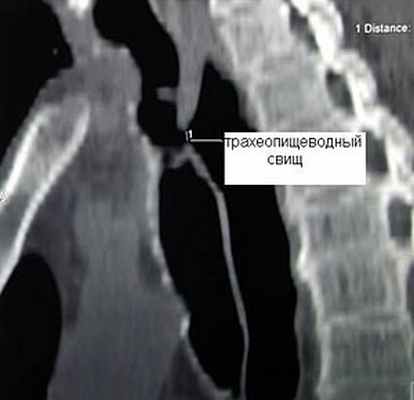

Трахеопищеводные свищи

Наиболее часто трахеопищеводные свищи возникают у больных раком пищевода при распаде опухоли, прорастающей в трахею. Другими причинами являются ранения пищевода и трахеи, перфорация пищевода при его бужировании по поводу рубцовых стриктур, пролежень от трахеостомической и интубационной трубок при длительной искусственной вентиляции легких.

Частота трахеопищеводных свищей не превышает 0,5% среди больных, которым проводилась длительная искусственная вентиляция легких. Как правило, трахеопищеводные свищи у этой группы больных возникают от избыточного давления манжетки интубационной трубки или давления дистального конца трахеостомической трубки на заднюю стенку трахеи при наличии в пищеводе зонда для энтерального питания, что приводит к ее ишемии, некрозу и образованию соустья между пищеводом и трахеей. Часто трахеопищеводные свищи сочетаются со стенозом трахеи, что существенно осложняет лечение таких больных. Заброс пищи в трахею приводит к гнойному трахеобронхиту с последующим развитием абсцедирующей пневмонии, что значительно ухудшает прогноз заболевания. Питание у такого рода больных через рот исключается. Адекватное питание больного обеспечивается через энтеральный зонд или гастростому. Учитывая, что консервативное лечение больных с трахеопищеводными свищами малоэффективно, единственным радикальным способом ликвидации свища неопухолевой природы является оперативное вмешательство.

Клиническая диагностика трахеопищеводных свищей, как правило, не вызывает трудностей. Проявляются они приступообразным кашлем, который возникает во время приема пищи. Однако уточнение их локализации при рентгенологическом исследовании с барием и эзофагоскопии вызывает существенные трудности, особенно при небольших размерах свища. Более информативным оказывается трахеоскопия, при которой удается определить размеры свища, расстояние от голосовых связок и карины. Кроме того, значительную помощь в выявлении трахеопищеводных свищей оказывает также компьютерная томография.

![]() Рис.9. Компьютерная томограмма больного с трахеопищеводным свищом. | ![]() Рис. 10. Трахеоскопия больного с трахеопищеводным свищом, осложненным стенозом трахеи. |

Радикальным методом лечения трахеопищеводных свищей является разъединение пищевода и трахеи с ушиванием дефектов в них и интерпозицией мышц между ними, обычно участка грудиноключичнососцевидной мышцы.